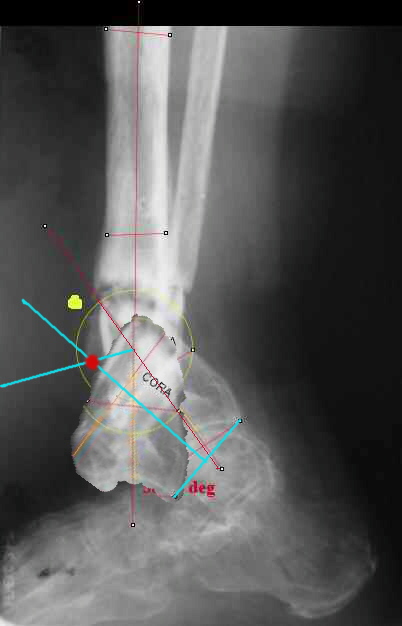

The right hinge point to simultaneously correct deformity and shortening will be the crossing point between the bissectrice of the complementary

angle of deformity and the perpendicular at the middle of the line connecting the departure and arrival place of one point of the bone structure you are correcting (see sketch.

You can see it better on http://clientes.netvisao.pt/nfrancac/preop01.htm